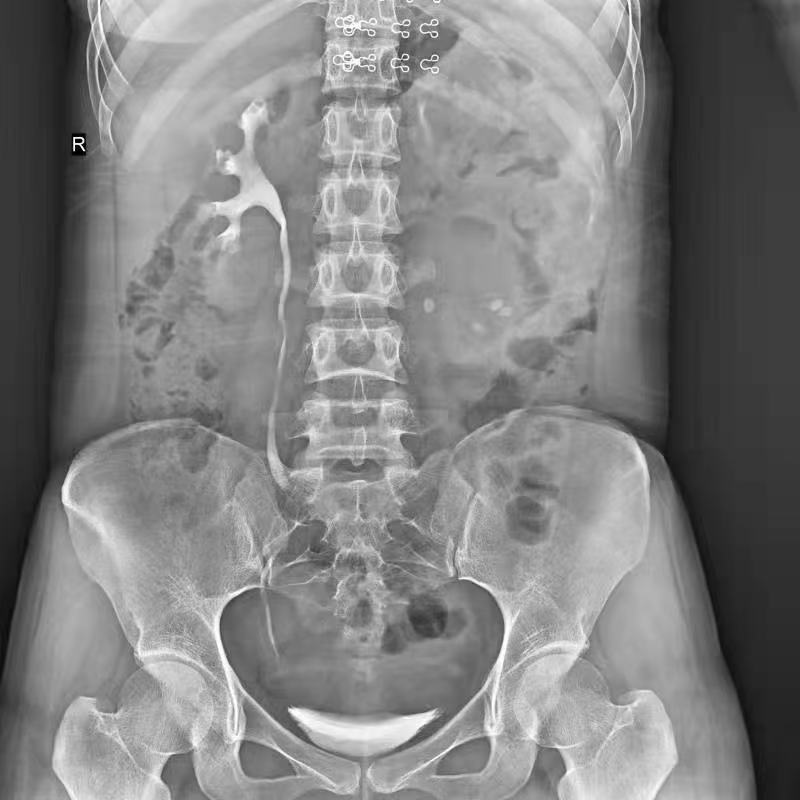

球管傾斜攝影角度-45°~45°,滿足臨床各部位各角度的攝影需求。如:髕骨軸位、頸椎正位、骶尾椎、鼻竇瓦氏位、梅氏位等部位檢查。

點片裝置移動范圍大,無需患者移動就能完成全身各部位的檢查;

床面橫向移動,輕松實現機動人不動。